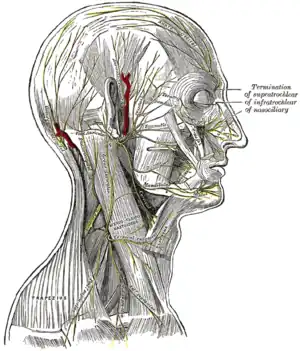

The nerves of the scalp, face, and side of neck. | |

Upon emerging from the stylomastoid foramen, the facial nerve gives rise to the posterior auricular branch. It then gives rise to the branch to the posterior belly of the digastric, and then the branch to the stylohyoid. The facial nerve then passes through the parotid gland, which it does not innervate, to form the parotid plexus. The nerve then bifurcates at the pes anserinus to become the upper and lower divisions of the facial nerve.[4] It then splits into five branches (temporal, zygomatic, buccal, marginal mandibular, and cervical) innervating the muscles of facial expression.[5][6]

Extracranial branches

Distal to stylomastoid foramen, the following nerves branch off the facial nerve:

- Posterior auricular nerve which controls movements of some of the scalp muscles around the ear

- Branch to posterior belly of digastric muscle

- Branch of the stylohyoid muscle

- Five major facial branches (at parotid plexus) – from superior to inferior: